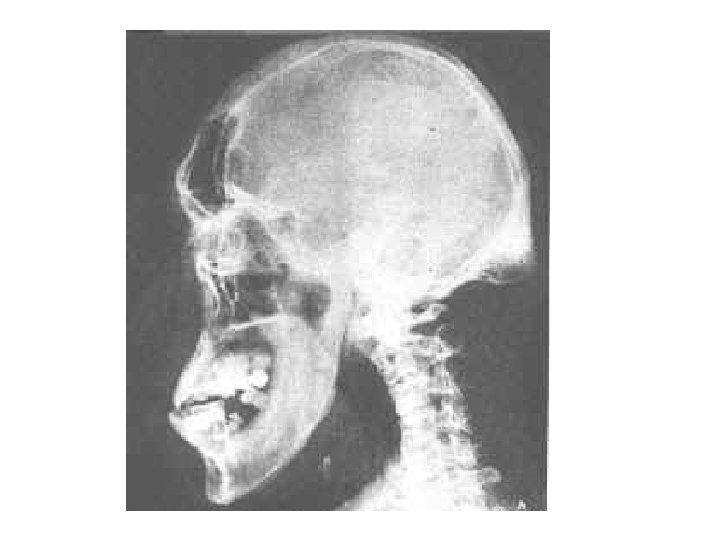

Acromegaly • Acromegaly is a serious condition that occurs when the body produces too much of the hormones that control growth. • The hormone most often affected is called growth hormone, or GH. Itハis produced by the pituitary gland, a tiny organ at the base of the brain. Growth hormone promotes growth of bone, cartilage, muscle, organs, and other tissues. • When there is too much growth hormone in the body, these tissues grow larger than normal. • This excessive growth can cause serious disease and even premature death.